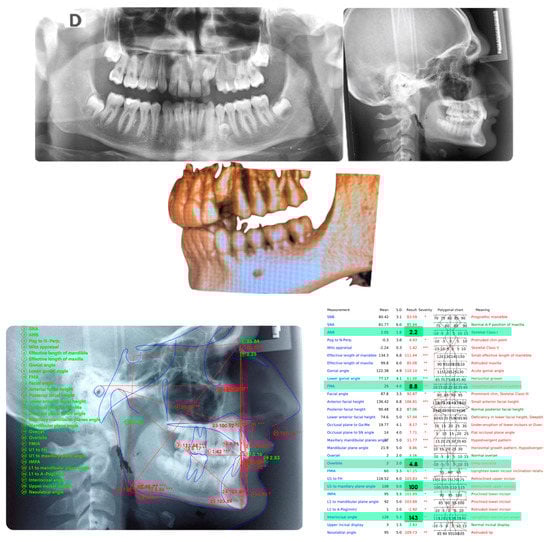

An adult female patient, 43 years old, with Class I occlusion on both sides and with a slight deep bite, light crowding, a persistent deciduous canine no. 63, and a horizontally impacted canine with the crown tip close to the lateral incisors and the tip of the root protruding beyond the buccal bone in the 2.3 area is presented in Figure 9 and Figure 10.

Class I occlusion on both sides with a slight deep bite, light crowding, a persistent deciduous canine no. 63, and a horizontally impacted canine with the tip of the crown close to the lateral incisors and the tip of the root protruding beyond the buccal bone in the 2.3 area.

Figure 10.

CBCT pictures of the patient. Since the patient was subjected to periodic radiographic control as she was a cancer survivor, the decision was to do a CBCT to receive all the informations useful for the deimpaction treatment and avoid conventional orthodontic X-rays like panoramic and lateral X-rays.